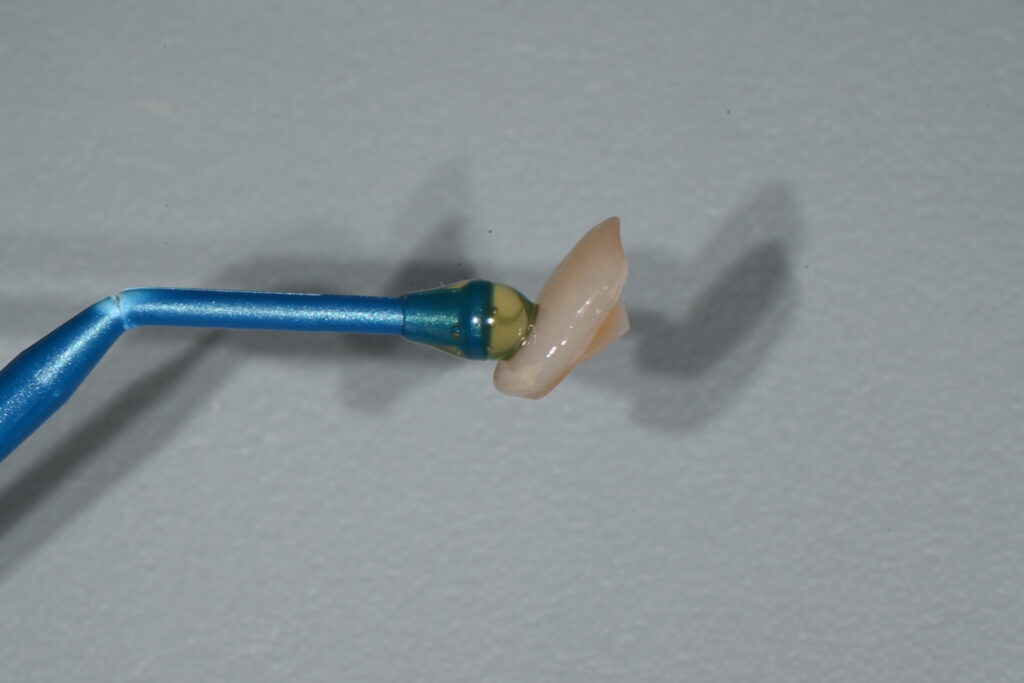

이렇게 준비가 되면 환자의 개인 색상에 맞는 라미네이트 색상을 선택하게 됩니다

치아의 색상을 선택하는 과정

각자 치아의 색상 피부의 톤이 다르기 때문에

이렇게 하나하나 선택이 필수입니다

라미네이트에서 제일 중요한 부분은 접착

라미네이트에서 제일 중요한 부분은 무엇일까요? 아름다움?아닙니다

일반환자분들은 이쁘게가 중요하지만 치과의사 입장에서 제일 중요한 부분은 바로 접착

즉 떨어지지 않게 제작하고 붙이는 과정입니다

오늘은 대부분의 치과에서 하지 않는 라미네이트 접착의 표준을 설명드리겠습니다

라미네이트 접착은 단순히 10분만에 붙이는 그런 과정이 아닙니다

접착의 과정은 거의 한시간이 걸리고 마취를 해야하는 고난이도의 과정입니다

붙이기 전 라미네이트는 깨지기 너무나 쉽지요

조심해야 합니다 그리고 색상과 모양도 봐야하는 번거로움이 있습니다